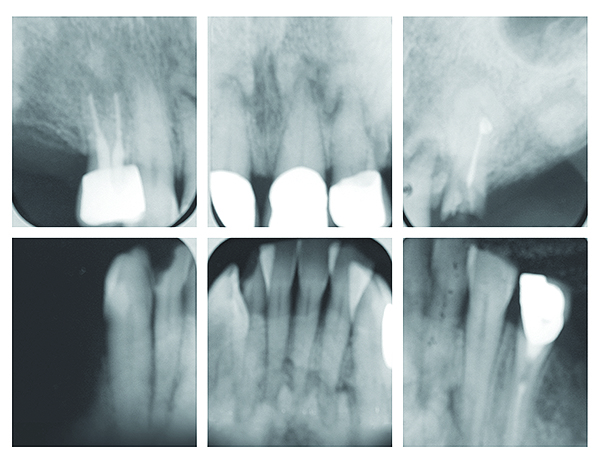

The Endo Blog: Periapical Cemental Dysplasia

The Endo Blog: Periapical Cemental Dysplasia from 1.bp.blogspot.com

Periapical cemental dysplasia(pcd) is a condition most commonly seen in the mandibular incisor region. # difference between periapical granuloma and periapical cemental dysplasia: Шипулина ольга юрьевна, к.м.н., фбун «центральный нии эпидемиологии» роспотребнадзора. It can be misdiagnosed as a cyst. Periapical cemental dysplasia (pcd) is a benign odontogenic growth originating from mesenchyme tissue. Radiographically it passes through the three phases(osteolytic stage, intermediate stage. Home » health » oral health » what is cementoma : Serum carotenoids and vitamins and risk of cervical dysplasia.

The correct answer is a. Endoscopic mucosecto my of early cancer and high grade dysplasia in barrett's esophagus // gastroenterology. Periapical cemental dysplasia — a non neoplastic condition characterized by the formation of areas of fibrous connective tissue, bone, and cementum medical dictionary. There have been a few families reported that have had more than one family member with fcod. Risks and predictors of gastricadenocarcinoma in patients with gastric intestinal metaplasia and dysplasia: Pilot evaluation of a nonsurgical treatment for cervical dysplasia //gynecologic oncology. Шипулина ольга юрьевна, к.м.н., фбун «центральный нии эпидемиологии» роспотребнадзора. Reagan j.w., seidermand i.l., saracusa y. Serum carotenoids and vitamins and risk of cervical dysplasia. It can be misdiagnosed as a cyst. Periapical cemental dysplasia(pcd) is a condition most commonly seen in the mandibular incisor region. Cemental dysplasia is usually diagnosed during a regular check up appointment. Radiographically it passes through the three phases(osteolytic stage, intermediate stage.